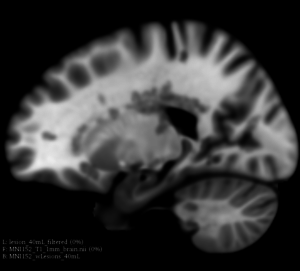

This extension offers a set of tools for brain lesion simulation, based on MRI images. At the moment, the module MS Lesion Simulator is available, where it can simulate both baseline scan lesion volumes (given a lesion load) and longitudinal image simulations. In summary, a statistical lesion database is generated based on a set of manual lesion mark-ups, being non-linearly registered to MNI152 space (isotropic 1mm of voxel resolution), and a local contrast ratio is applied on each imaging modality provided by the user. Using a small set of parameters (lesion load, lesion homogeneity, lesion intensity independence and lesion variability), it is possible to generate a broad range of MS lesions patterns in multimodal MRI imaging techniques (at moment, T1, T2, T2-FLAIR, PD, DTI-FA and DTI-ADC images are provided). For more details about this project, please see the original paper.